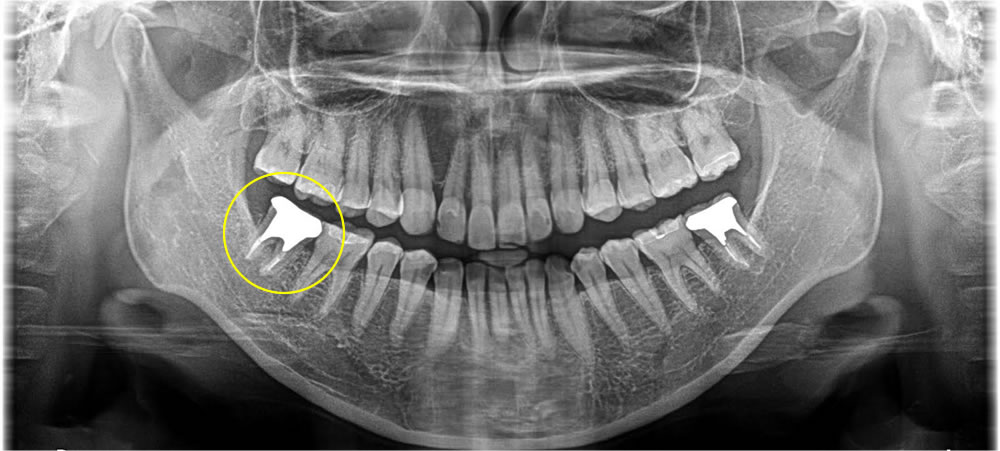

何もしていなくても歯が痛いという事で来院された患者さまです。CT写真を撮影し、診断したところ、分岐部病変、根尖嚢胞が確認できました。治療方針について患者さまと相談した結果、当該歯を抜歯してインプラント治療を希望されました。